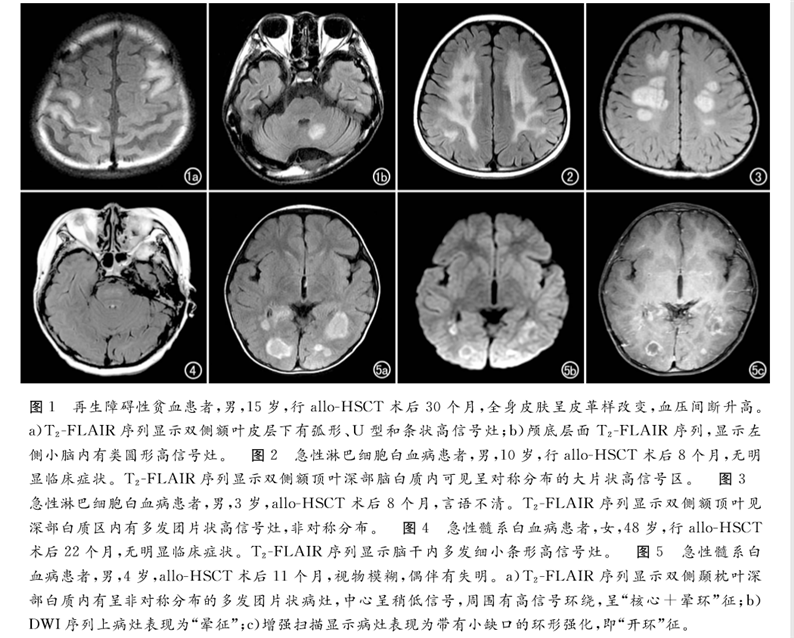

北京陸道培醫(yī)院影像科發(fā)表題為《血液病異基因造血干細(xì)胞移植后中樞神經(jīng)系統(tǒng)慢性移植物抗宿主病的MRI表現(xiàn)》的論文,該論文刊登在中文特種醫(yī)學(xué)類(lèi)核心期刊《放射學(xué)實(shí)踐》2019年12月第34卷第12期。

論文回顧性分析了2013年6月—2017年12月北京陸道培醫(yī)院確診為allo-HSCT后并發(fā)中樞神經(jīng)系統(tǒng)慢性移植物抗宿主病的12例血液病患者的臨床和影像學(xué)資料。得出結(jié)論,MRI是發(fā)現(xiàn)血液病異基因造血干細(xì)胞移植(allo-HSCT)后并發(fā)中樞神經(jīng)系統(tǒng)慢性移植物抗宿主病的有效手段,可以提高對(duì)本病的診斷及鑒別水平,為臨床制訂佳治療方案提供幫助。